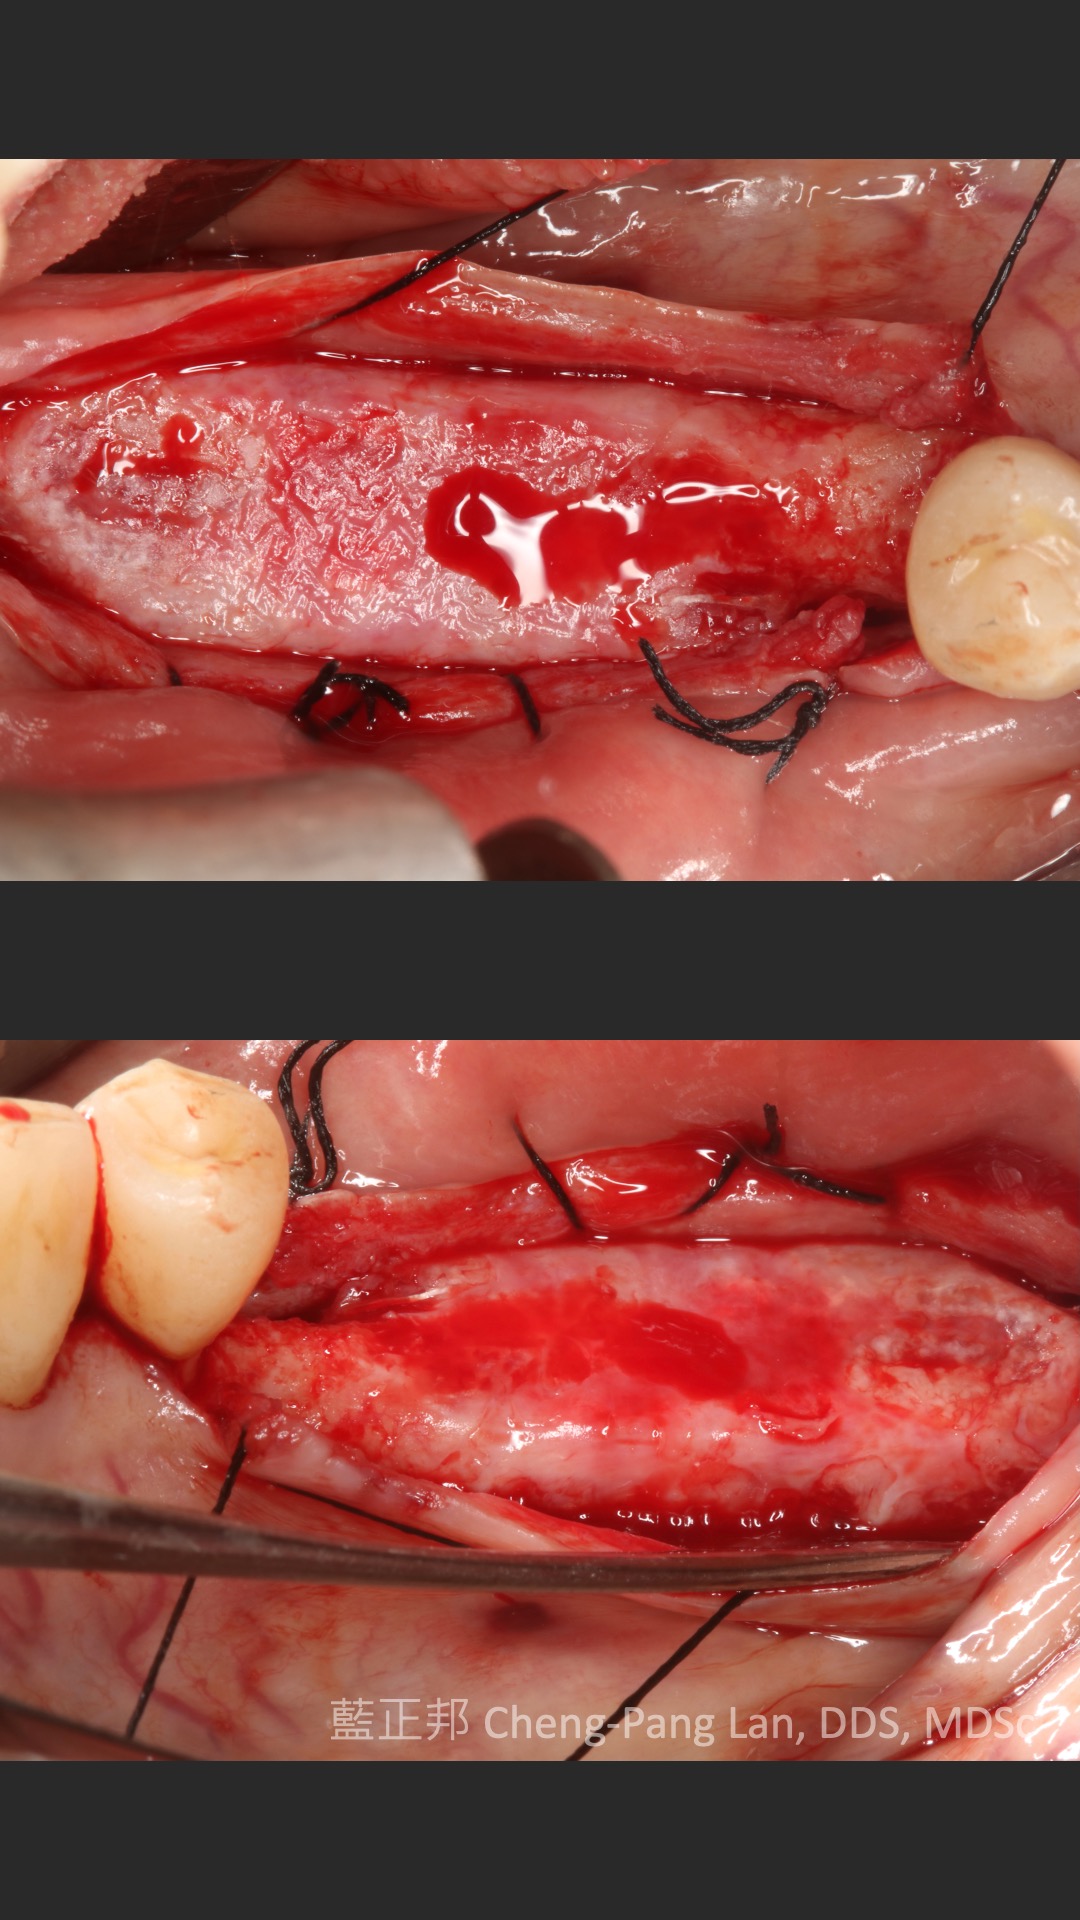

●第十一章垂直補骨,前一版的作者Massimo Simion,改成了Istvan Urban,果如我2016年判斷的,Istvan Urban已成為垂直補骨的接班人,連主編Buser也這麼認為(笑)。這邊寫的是簡易版,若朋友有興趣詳細的垂直補骨,直接看Urban寫的兩本垂直補骨書即可,我這邊也有第二本Vertical 2心得。但是十一章關於頰側與舌側的皮瓣鬆弛,寫得簡潔扼要,值得詳讀。